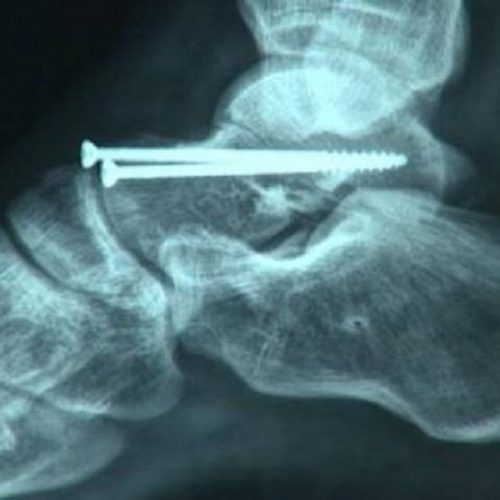

В Харьковском институте патологии позвоночника и суставов прооперировали 23-летнего Юрия Неудачина, ставшего одним из пострадавших в ДТП на Сумской. Об […]